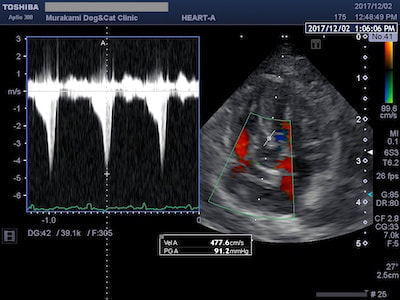

SAMによる左室流出路閉塞

異常な動きをする僧帽弁により左室流出路閉塞が起こると、左心室から流出する血流(大動脈血流)に高速血流が生じます(ホースの先端を摘むと水が勢いよく出るイメージ)。SAMの場合は左室流出血流波形がダガーシェイプ(ダガーナイフ型)になるのが特徴です。治療には左室流出路閉塞を緩和する目的で心拍数を抑えるお薬を使います。